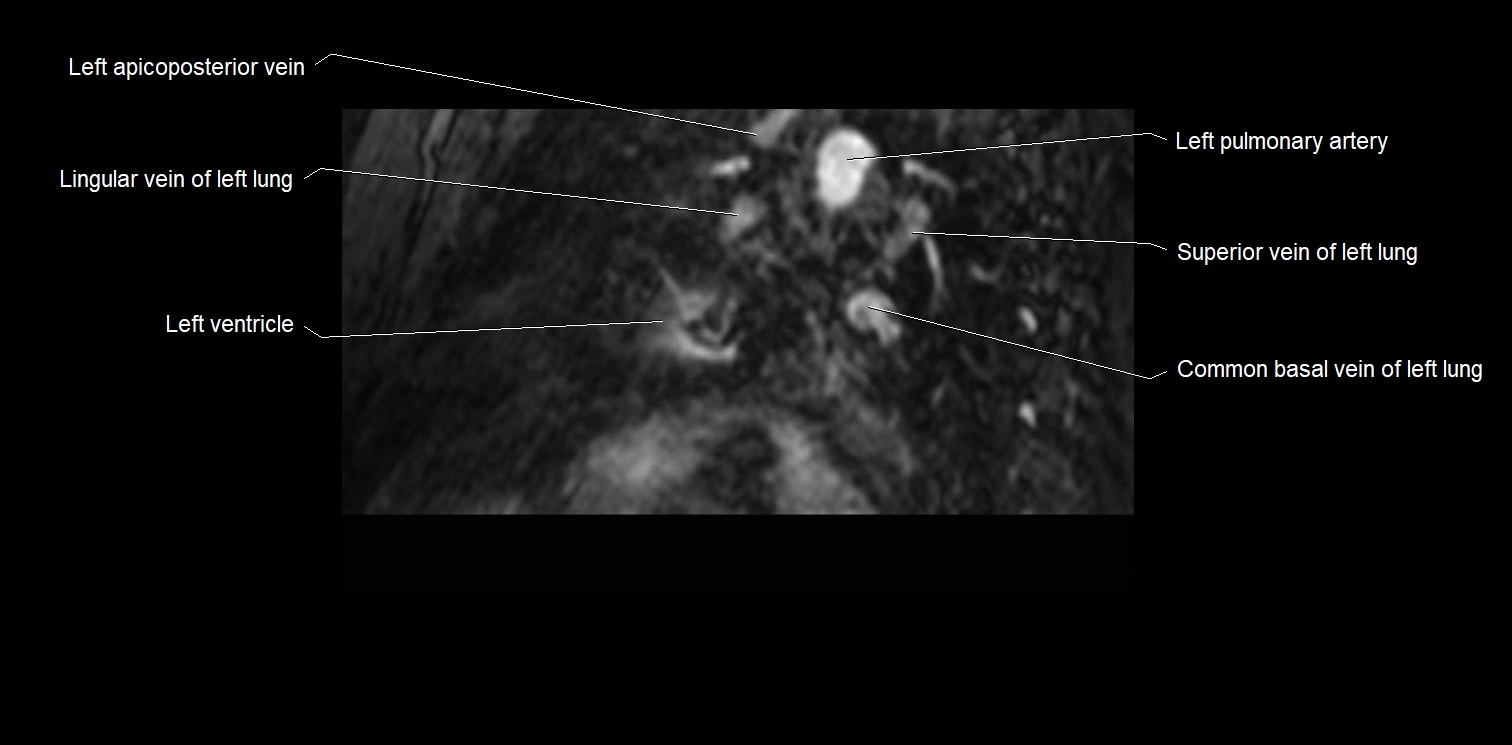

MRI image